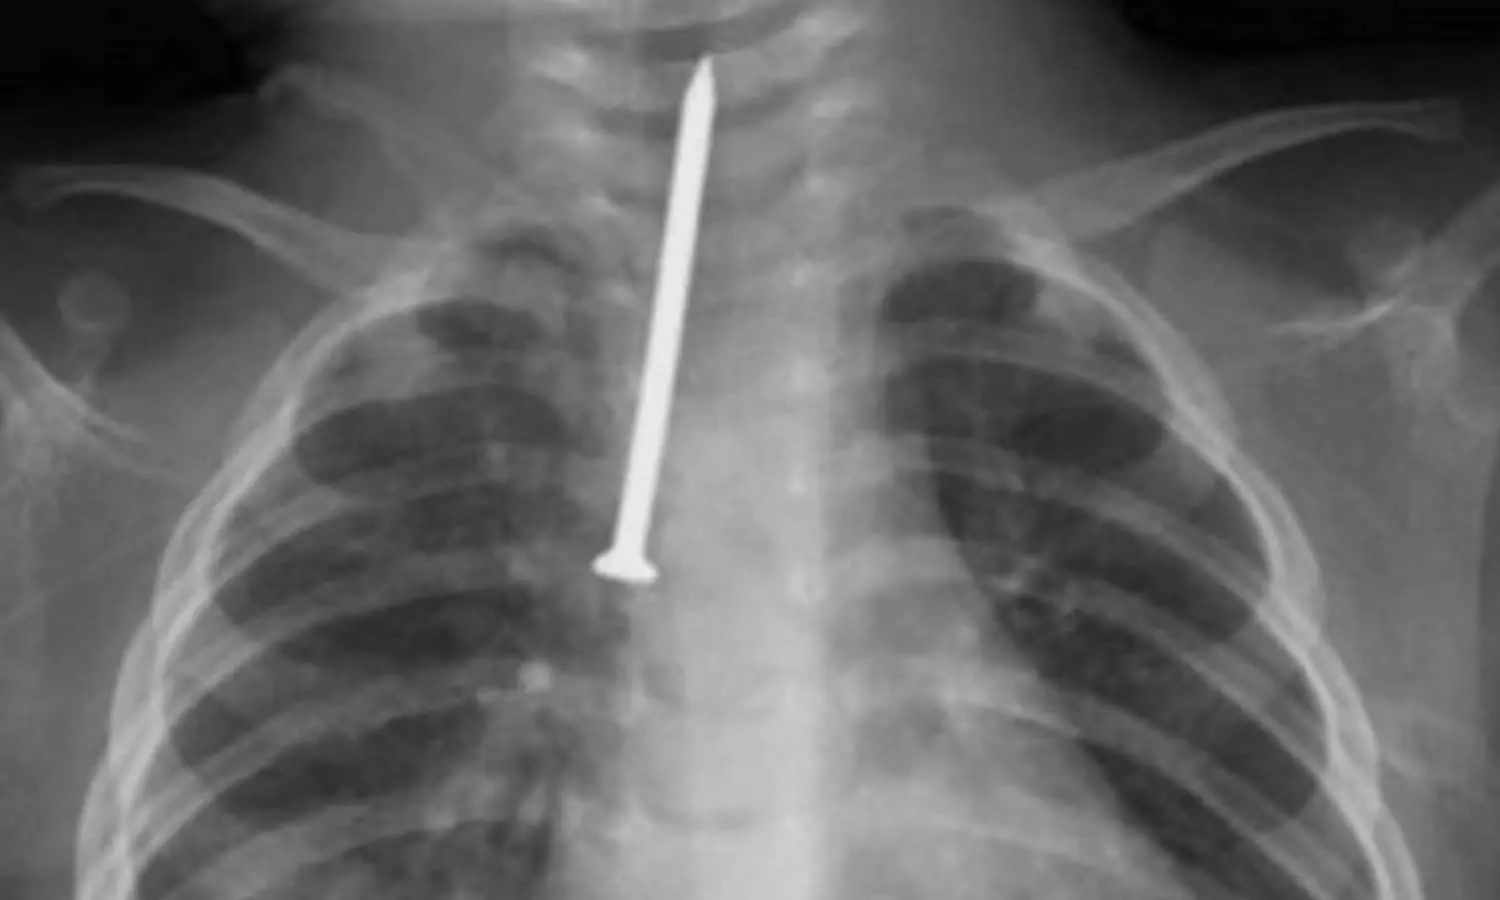

ശ്വാസനാളത്തിൽ കുടുങ്ങിയ ആണി പുറത്തെടുത്തു; റിയാദിൽ എട്ട് മാസം പ്രായമുള്ള കുഞ്ഞിന് പുതുജീവൻ

5 സെ.മീ നീളമുള്ള ആണിയാണ് പുറത്തെടുത്തത്

റിയാദ്: ശ്വാസനാളത്തിൽ അഞ്ച് സെ.മീ നീളമുള്ള ആണി കുടുങ്ങി അതീവ ഗുരുതരാവസ്ഥയിലായ എട്ടുമാസം പ്രായമുള്ള കുഞ്ഞിന് റിയാദിൽ പുതുജീവൻ. റിയാദിലെ കിങ് സൗദ് മെഡിക്കൽ സിറ്റി ഹോസ്പിറ്റലിലെ ഡോക്ടർമാരുടെ നേതൃത്വത്തിൽ നടത്തിയ അതി സങ്കീർണമായ ശസ്ത്രക്രിയയിലൂടെയാണ് കുഞ്ഞിന്റെ ജീവൻ രക്ഷിച്ചത്.

അബദ്ധത്തിൽ ആണി വിഴുങ്ങിയ കുഞ്ഞിന് ശ്വസിക്കാൻ കടുത്ത പ്രയാസം അനുഭവപ്പെട്ടതിനെത്തുടർന്നാണ് ആശുപത്രിയിൽ എത്തിച്ചത്. ആണി ശ്വാസനാളത്തിൽ തങ്ങിനിന്നത് കുഞ്ഞിന്റെ നില അതീവ ഗുരുതരമാക്കി. ഉടൻ തന്നെ കുഞ്ഞിനെ ഓപ്പറേഷൻ തിയറ്ററിലേക്ക് മാറ്റുകയും 'റിജിഡ് ബ്രോങ്കോസ്കോപ്പി' എന്ന അത്യാധുനിക സംവിധാനം ഉപയോഗിച്ച് ആണി പുറത്തെടുക്കുകയുമായിരുന്നു. തൊറാസിക് സർജറി വിഭാഗം മേധാവി ഡോ. മുഹമ്മദ് അൽ അംസിയുടെ നേതൃത്വത്തിലുള്ള വിദഗ്ധ സംഘമാണ് ശസ്ത്രക്രിയ നടത്തിയത്.